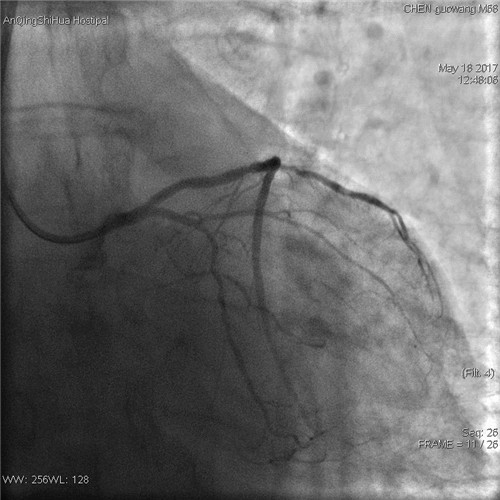

術(shù)后 回旋支血流通暢